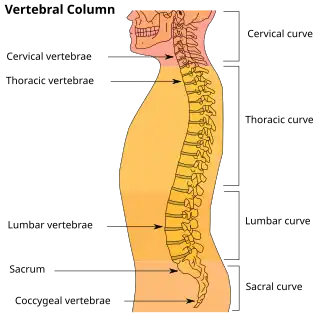

In human anatomy, the five vertebrae are between the rib cage and the pelvis. They are the largest segments of the vertebral column and are characterized by the absence of the foramen transversarium within the transverse process (since it is only found in the cervical region) and by the absence of facets on the sides of the body (as found only in the thoracic region). They are designated L1 to L5, starting at the top. The lumbar vertebrae help support the weight of the body, and permit movement.

Shape of lumbar vertebrae (shown in blue and yellow). Animation. Vertebral column.

Vertebral column

Vertebral column Illustration highlighting lumbar spine.

Illustration highlighting lumbar spine. A lumbar vertebra seen from the side